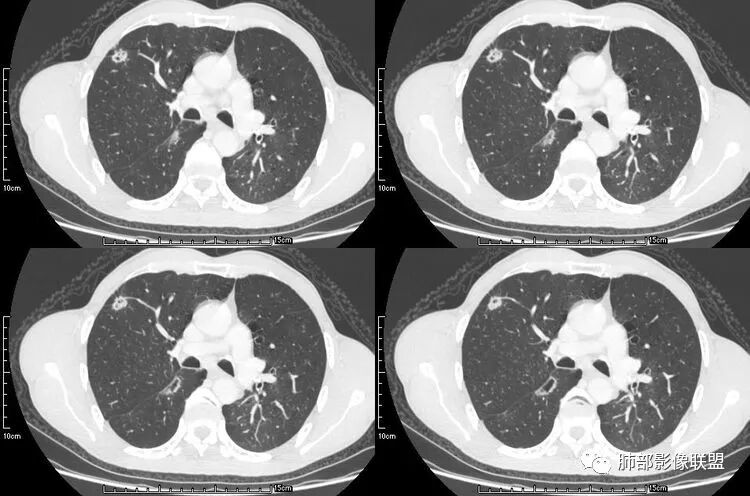

老年男性,咳嗽,咳痰带血2月,左下肺可见一团块影,深分叶,胸膜牵拉,可见坏死,坏死边界清,考虑恶性,双肺多发散在结节影,可见分叶,空洞,胸膜牵拉,考虑转移瘤;

患者老年男性,咳嗽、咳痰、痰中带血伴胸闷2月余。长期大量吸烟史。查肝肾功能、血糖、血脂、心肌酶、电解质、血沉、C反应蛋白、抗“O”、类风湿因子、抗核抗体谱无明显异常。肿瘤标志物提示NSE、CYFRA21-1稍升高。胸部CT:肺气肿背景,左肺下叶后基底段不规则肿块影,见支气管截断,内见大片状低密度区及部分血管影,增强轻度强化,远端空洞形成。双肺多发不规则实性结节影、见毛刺、胸膜牵拉及血管集束,结节内见空洞形成,部分可见血管影,多位于胸膜下。双肺见多发肺大泡。综合考虑左下肺恶性病变并双肺转移。鳞癌或淋巴瘤可能。鉴别血管炎性病变及真菌感染。

张延军:双肺多发结节,空洞影,后者洞壁厚薄不均匀,部分腔内丝丝落落,呈分叶征,边缘见毛刺影,病灶大部分位于胸膜下,与血管相连,右肺下叶前基底段结节近段支气管截断,远端见空腔。左肺下叶病灶密度不均,背段支气管壁增厚,管腔狭窄。考虑1.双肺下叶占位性病变伴肺内空洞性转移 2.多原发的占位 3.肉芽肿性血管炎代排。

本病例左肺下叶肿块,有深分叶、毛刺、胸膜牵拉凹陷、支气管截断及纵隔内淋巴结肿大等征象,都均支持病灶为恶性,如腺癌,而且叶间裂的多发结节也提示是腺癌来源可能大;双肺多发结节、肿块,大部分病灶有分叶、毛刺及胸膜凹陷的恶性征象,与原发肿瘤本身的性质有关,所以应该与左肺下叶肿块同源,而且双肺多发病灶内空洞也具有多样性;